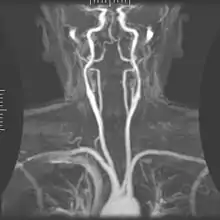

Angiography

Magnetic resonance angiography

Magnetic resonance angiography (MRA) generates pictures of the arteries to evaluate them for stenosis (abnormal narrowing) or aneurysms (vessel wall dilatations, at risk of rupture). MRA is often used to evaluate the arteries of the neck and brain, the thoracic and abdominal aorta, the renal arteries, and the legs (called a "run-off"). A variety of techniques can be used to generate the pictures, such as administration of a paramagnetic contrast agent (gadolinium) or using a technique known as "flow-related enhancement" (e.g., 2D and 3D time-of-flight sequences), where most of the signal on an image is due to blood that recently moved into that plane (see also FLASH MRI).[47]

Techniques involving phase accumulation (known as phase contrast angiography) can also be used to generate flow velocity maps easily and accurately. Magnetic resonance venography (MRV) is a similar procedure that is used to image veins. In this method, the tissue is now excited inferiorly, while the signal is gathered in the plane immediately superior to the excitation plane—thus imaging the venous blood that recently moved from the excited plane.[48]